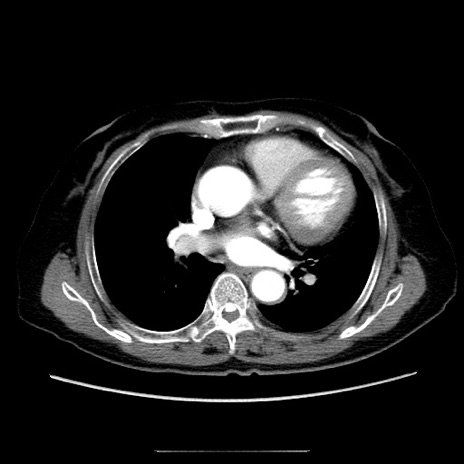

【症例】70歳代女性

【主訴】お腹が張る

【現病歴】1週間くらい前から腹部膨満の自覚あり。昨日夜から増悪したため、本日救急外来受診。

【身体所見】意識清明、BT 36.5℃、BP 165/106mmHg、HR 80bpm、SpO2 98%、腹部:膨満、軟、自発痛・圧痛なし、触診にて不快感あり、腸蠕動音:減弱

【データ】WBC 12600、CRP 1.04